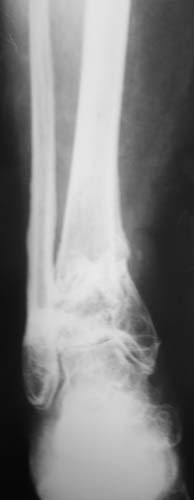

Женщина, 62 года. Травма 2 года назад в результате ДТП. Находится на лечении с 30.10.06 года с диагнозом: Несросшийся перелом дистальной трети правой большеберцовой кости с угловыми деформациями дистального отдела конечности, дефектом костной ткани.

Рубцовой деформацией мягких тканей медиальной поверхности дистальной трети голени. Нейротрофические нарушения. Посттравматический остеопороз. Дегенеративно-дистрофический остеоартроз правого голеностопного сустава.Сопутствующая патология.: ЖКБ, хронический калькулезный холецистит в стадии ремиссии. МКБ, хронический пиелонефрит в стадии ремиссии.Ожирение 3 ст. Посттромбофлебитический синдром нижних конечностей, ХВН 2 ст. Посттравматическая нейропатия левого малоберцового нерва с парезом левой стопы. Какие предложения по тактике лечения? Заранее благодарю!

Можно после остеотомии м\б кости сделать интрамедулярный остеосинтез-артродез, забив штифт снизу через пятку. Для этого хорошо подходит короткий дистальный бедренный гвоздь Chm. дистальные винты заводить сзади в сагитальной плоскости в пяточную и таранную кости.

Голеностопный сустав тут, видимо, потерян. Так что надо думать только про стабилизацию. Какие из существующих вариантов артродеза доступны, и какой из доступных оптимален? Антон, есть ли смысл обсуждать варианты с закрытым штифтованием, доступно оно? Если да, то Алексей Семенистый предлагает вполне жизнеспособный план (хотя можно и антгерадно сделать). Если нет, то надо что-то придумывать с аппаратом. Наверно, латеральным доступом кпереди от fibula с ее пересечением открыться, и что-то костно-пластическое делать.